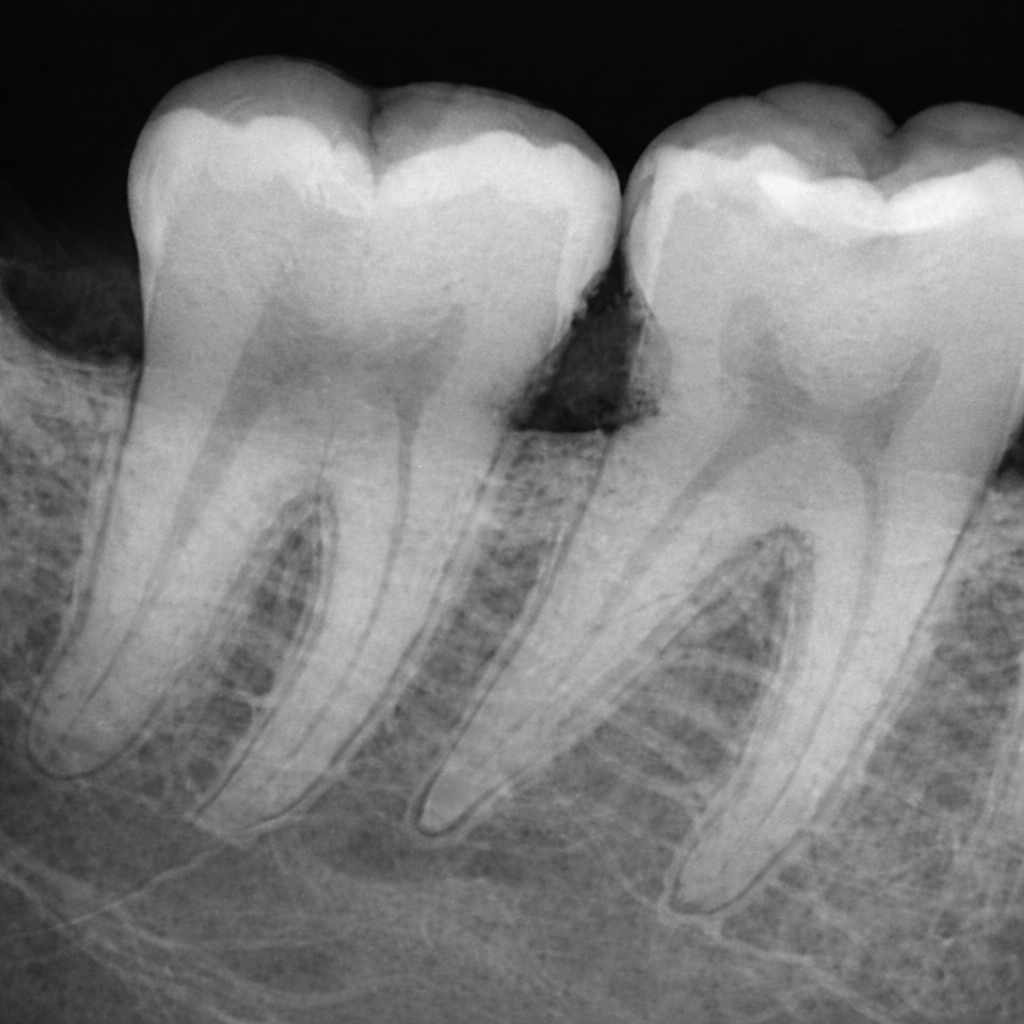

Aparición de caries o sensibilidad dental persistente

La presencia continua de molestias ante frío, calor o dulce puede indicar un daño progresivo en el esmalte que requiere tratamiento.

• Empastes u obturaciones para tratar caries